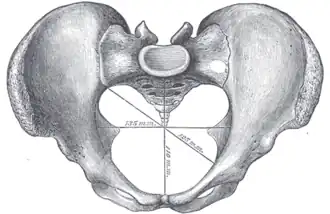

A distinction is made between the lesser or true pelvis inferior to the terminal line, and the greater or false pelvis above it. The pelvic inlet or superior pelvic aperture, which leads into the lesser pelvis, is bordered by the promontory, the arcuate line of ilium, the iliopubic eminence, the pecten of the pubis, and the upper part of the pubic symphysis. The pelvic outlet or inferior pelvic aperture is the region between the subpubic angle or pubic arch, the ischial tuberosities and the coccyx. [3]

Alternatively, the pelvis is divided into three planes: the inlet, midplane, and outlet.[4]

Caldwell–Moloy classification

Throughout the 20th century pelvimetric measurements were made on pregnant women to determine whether a natural birth would be possible, a practice today limited to cases where a specific problem is suspected or following a caesarean delivery. William Edgar Caldwell and Howard Carmen Moloy studied collections of skeletal pelves and thousands of stereoscopic radiograms and finally recognized three types of female pelves plus the masculine type. In 1933 and 1934 they published their typology, including the Greek names since then frequently quoted in various handbooks: Gynaecoid (gyne, woman), anthropoid (anthropos, human being), platypelloid (platys, flat), and android (aner, man).[44][45]

However, Caldwell and Moloy then complicated this simple fourfold scheme by dividing the pelvic inlet into posterior and anterior segments. They named a pelvis according to the anterior segment and affixed another type according to the character of the posterior segment (i.e. anthropoid-android) and ended up with no less than 14 morphologies. Notwithstanding the popularity of this simple classification, the pelvis is much more complicated than this as the pelvis can have different dimensions at various levels of the birth canal.[48]

Nowadays obstetric suitability of the female pelvis is assessed by ultrasound. The dimensions of the head of the fetus and of the birth canal are accurately measured and compared, and the feasibility of labor can be predicted.

Diameters of pelvic inlet